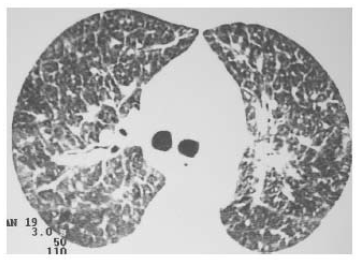

Uma paciente de 49 anos de idade, sem antecedentes patológicos conhecidos, com tabagismo importante (80 anos-maço) e com importante perda de peso nos últimos meses, compareceu a uma consulta ambulatorial apresentando dispneia progressiva associada a dessaturação em ar ambiente. Negou febre ou outros sintomas. No exame físico, constatou-se que a paciente apresentava saturação de 85% a.a., sem sinais de desconforto respiratório e com importante baqueteamento digital. Foi encaminhada ao setor de imagem, onde realizou tomografia computadorizada de tórax com um dos cortes representados na figura a seguir.

A paciente apresentava baciloscopia negativa e CEA acima do percentil 99 do teste.

Com base nesse caso hipotético, assinale a alternativa que apresenta a principal etiologia a ser considerada para essa paciente.